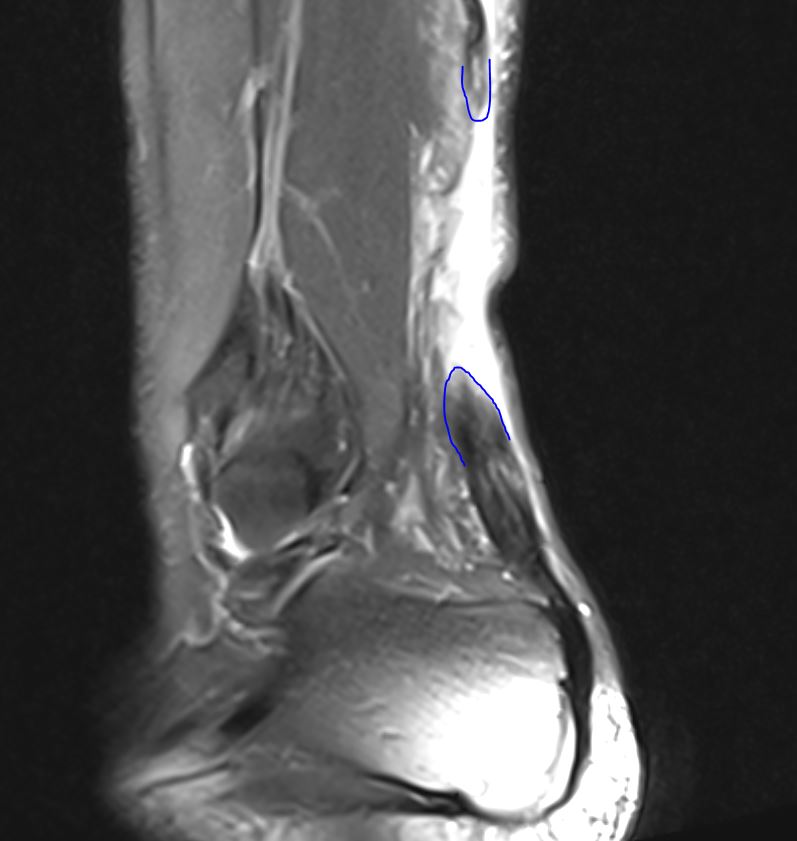

frische Achillessehnenruptur